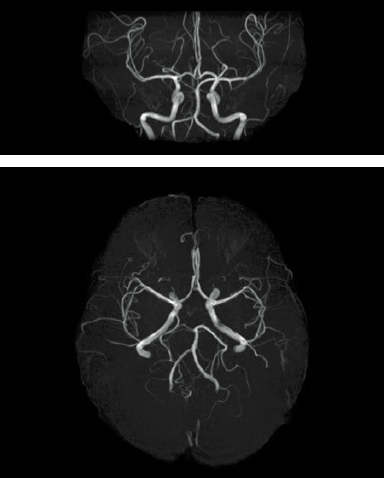

Digital image processing function that automatically creates clipping images of head MRA images.

When AutoExam is executed, clipping is performed automatically after MRA imaging.

It is possible to perform additional clipping on images after automatic clipping.

MRA

without clipping

with AutoClip